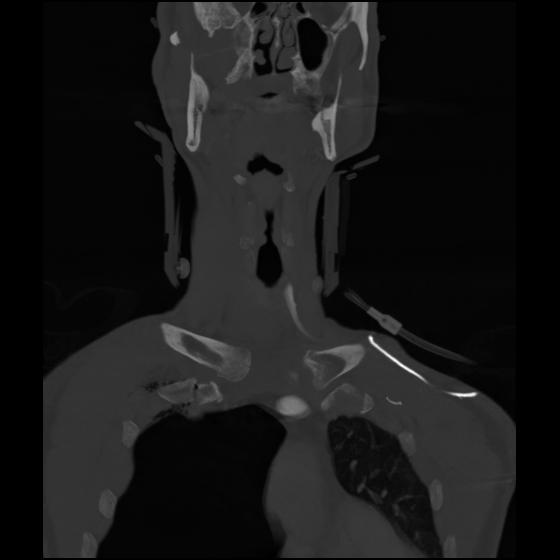

23 ANGIO,CE,Cor-MIP,5.000,ANGIO,Cor-MIP,